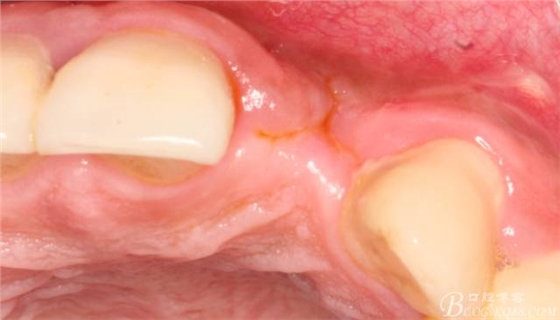

事實(shí)證明,我的做法沒(méi)有錯(cuò)誤,一個(gè)月后,軟組織健康愈合。鄰牙軟組織沒(méi)有退縮。

再次翻瓣。